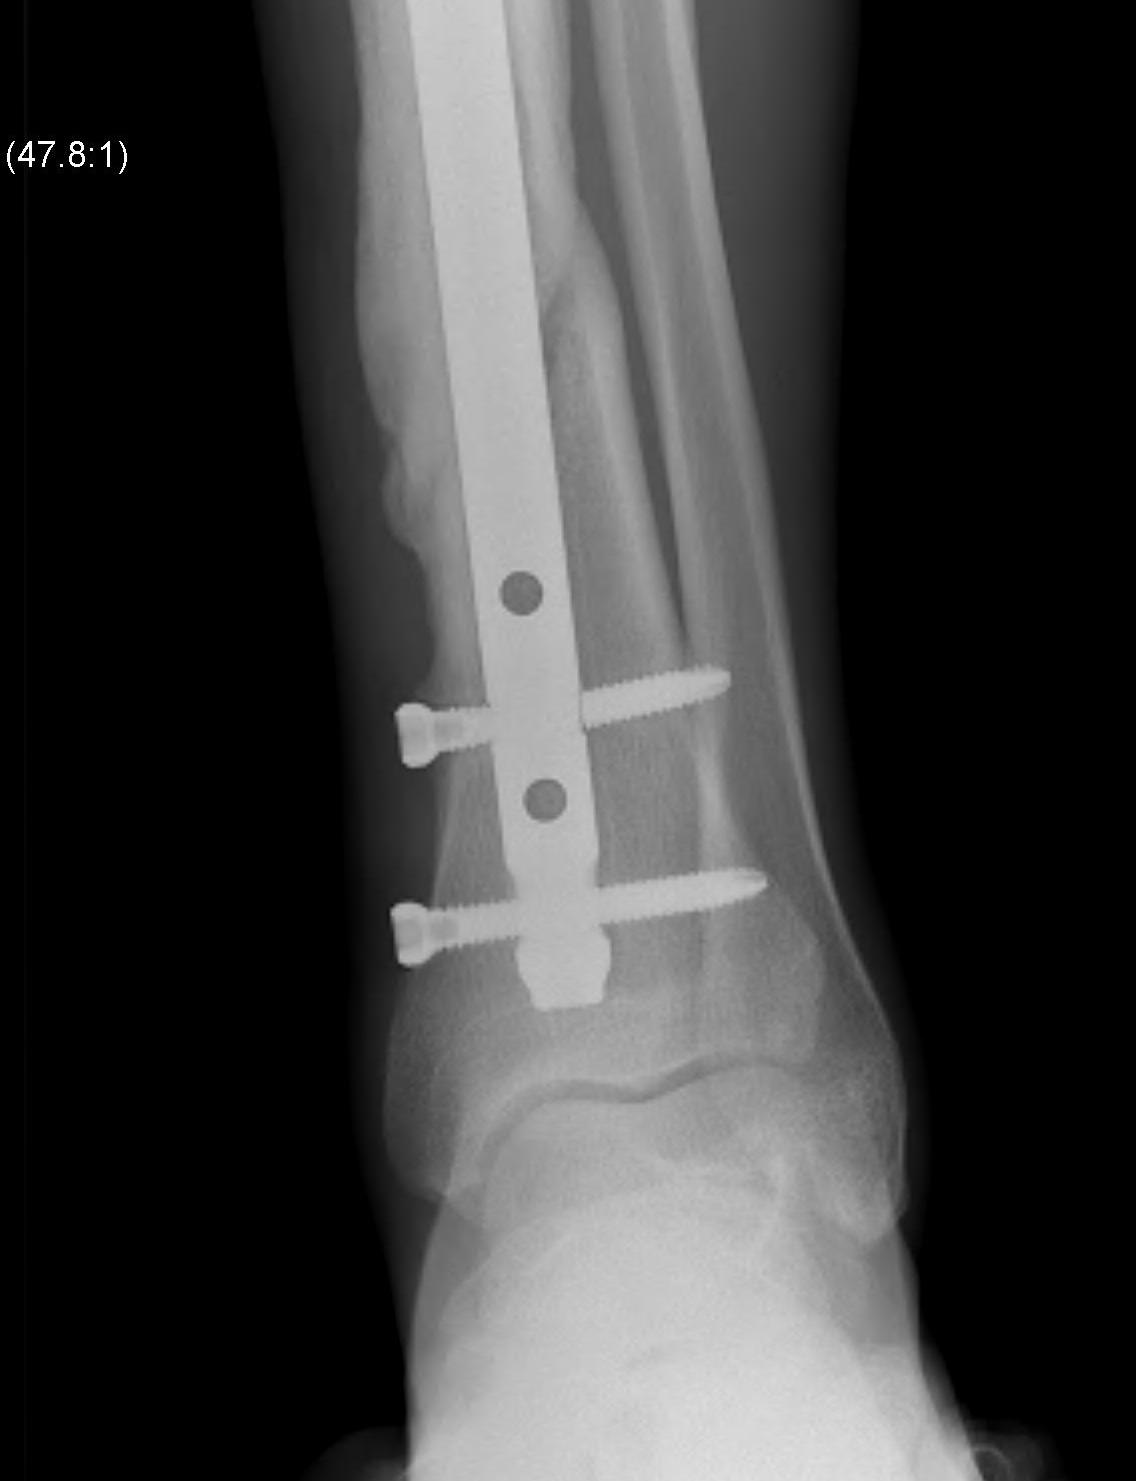

Intra-medullary Nail

Indications

- wounds / soft tissues not suitable to plate

- relatively stable

- sufficient distal bone

Design

Distal tibial nails

- multiple distal screws

- usually 2 medial-lateral and 1 AP

- most distal screw within 5 mm of end of nail

Technique

Consider semi-extended suprapatella nail

- easier to reduce fracture

- easier to get AP and lateral fluoroscopy

Most important is to centre guide wire over talus

- in lateral and AP

- use finger reduction tools and pass across fracture site to exact centre in AP and lateral

- bone reduction forceps

- blocking screws

- universal external fixation

- plate fibula

Fibular fixation